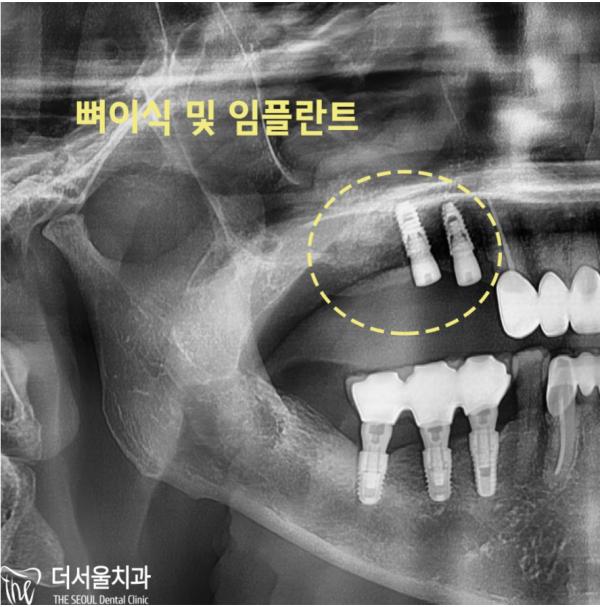

네비게이션 임플란트 진단을 통해 상악동에 있는 염증을 확인하고

골질까지 확인할 수 있었습니다. 뼈가 얇아져 있어 임플란트를 심기 어려워

상악동 거상술 후 뼈이식을 하기로 하였습니다.